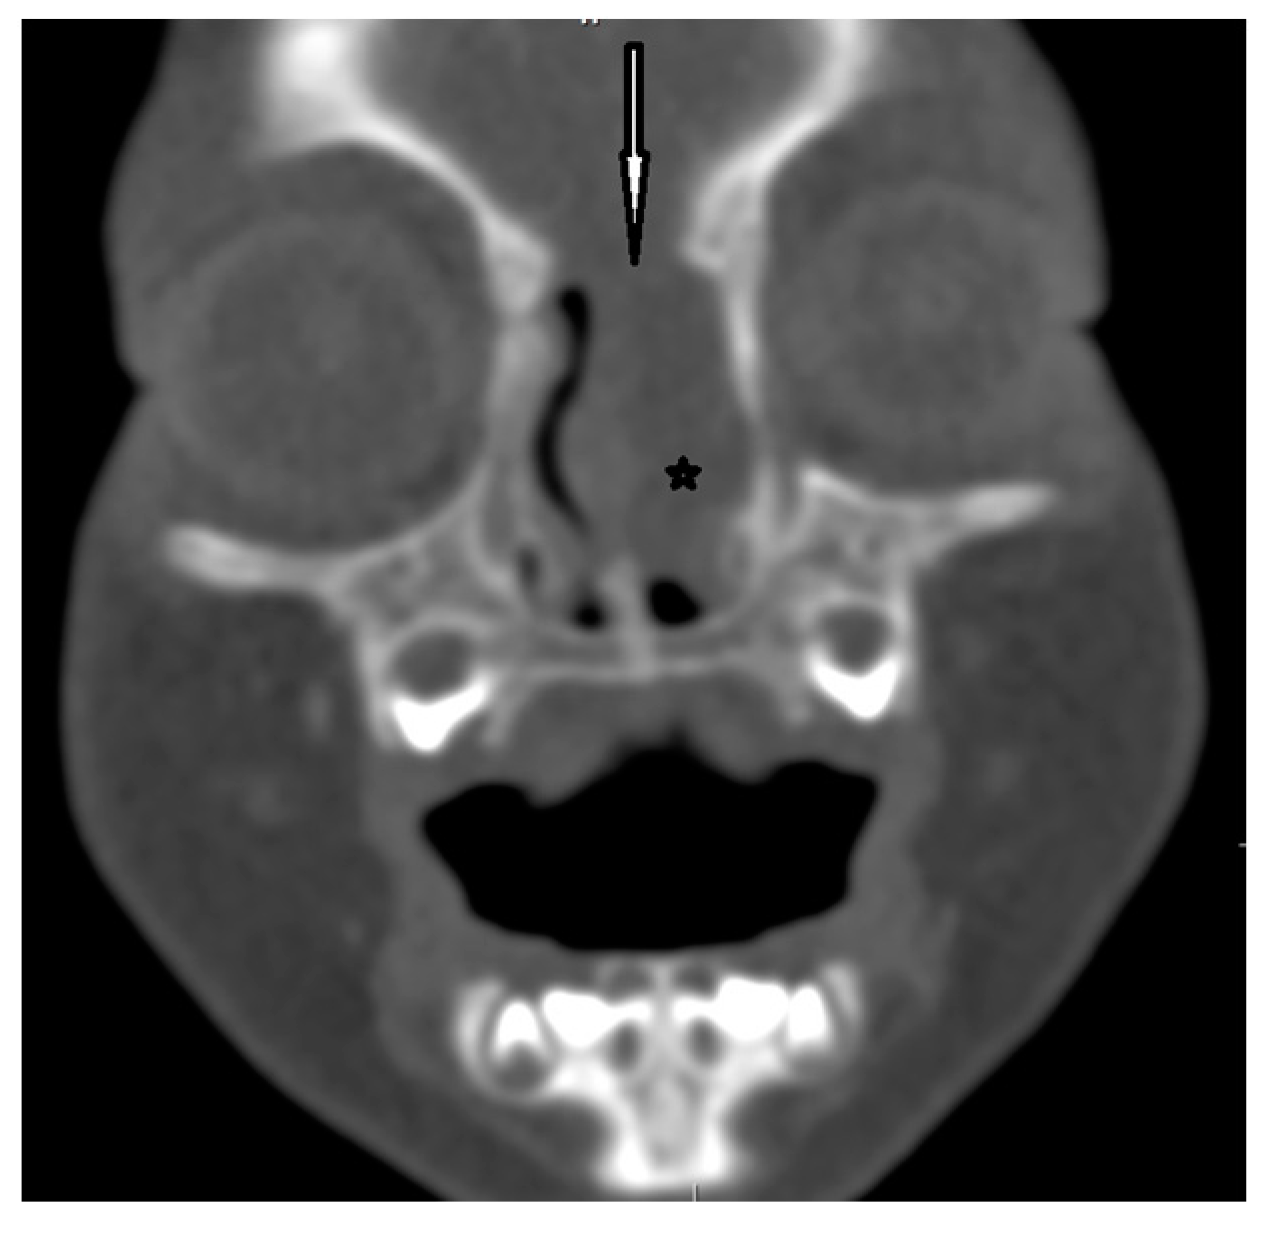

| Radiological characteristics | CT | No correlation between the particular location of the sinus ostium or cyst and the presence of intracranial extension; bifid crista galli and widening of foramen caecum (suggestive of intracranial extension); dermoid cyst—density of fat; epidermoid cyst—density of water | Bony defect may be revelaed | Developmental bony defect of the skull base |